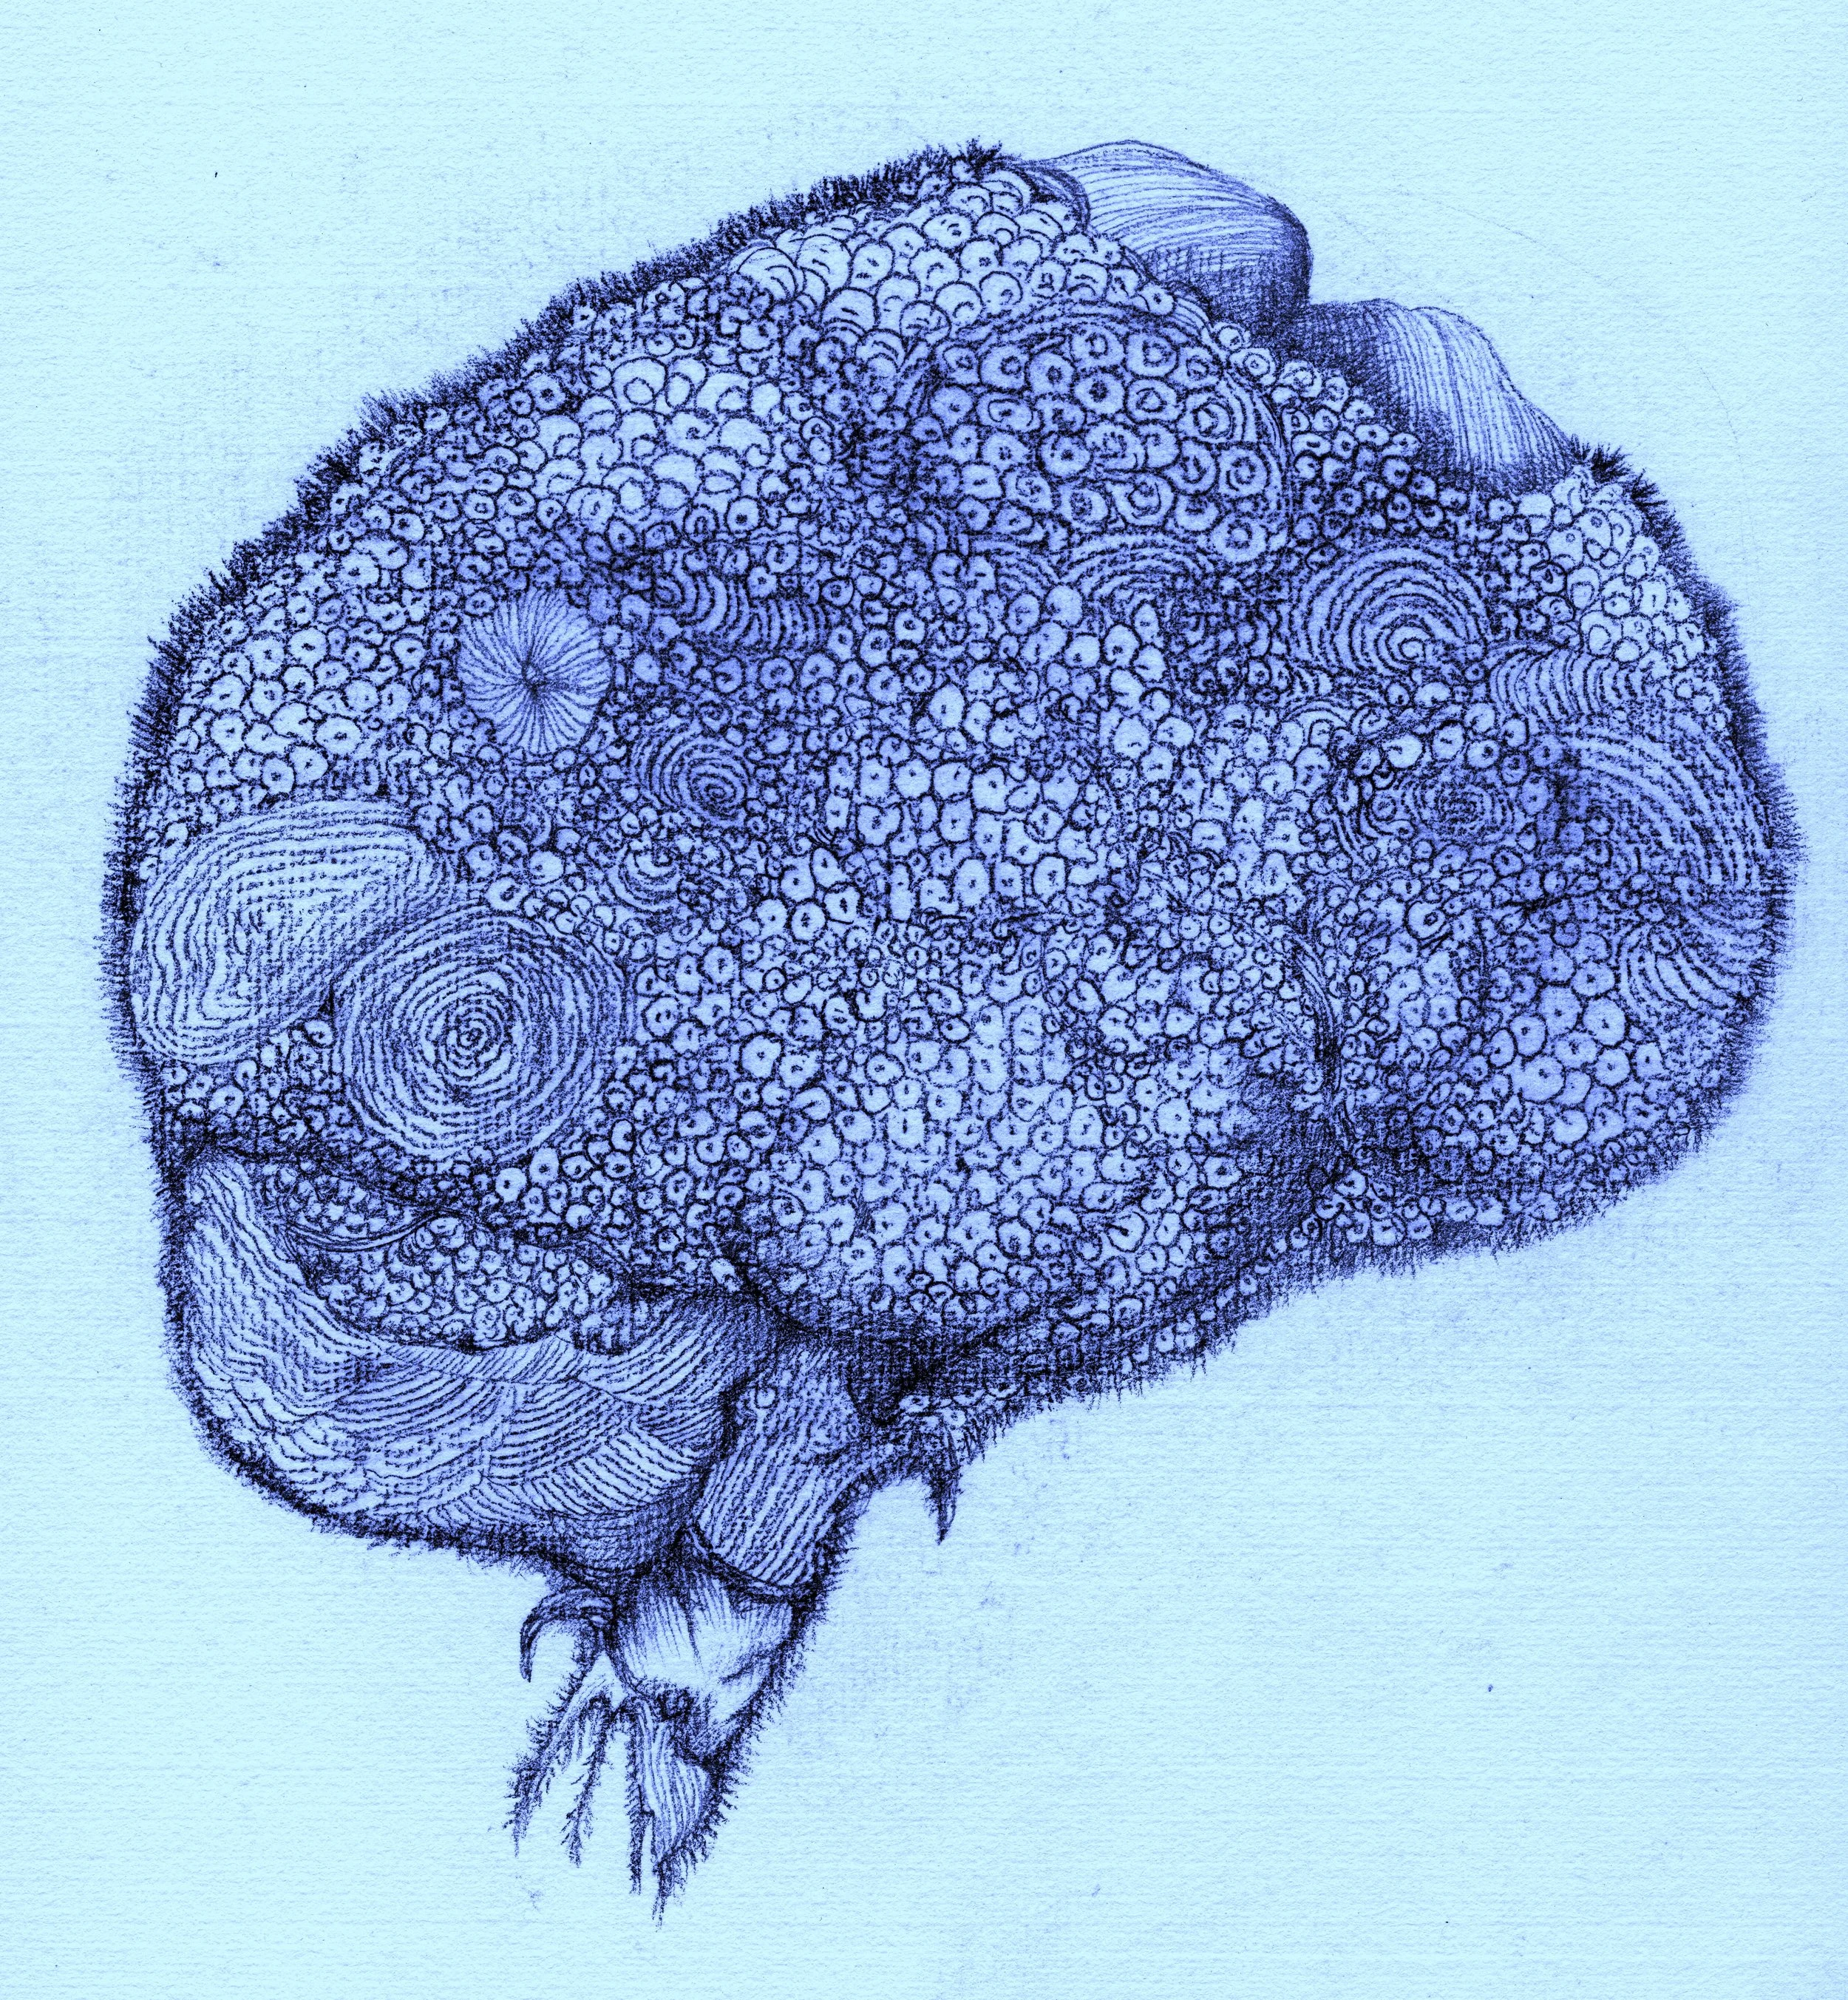

腦梗(Cerebral infarction)

Vegetative Brain (植腦)

Brain Fog 1 (腦霧)

Brain Fog 2(腦霧)

Brain Fog 3 (腦霧)

Brain Fog 4(腦霧)

Brain Fog 5 (腦霧)

Brain Fog 6(腦霧)

Brain Fog 7(腦霧)